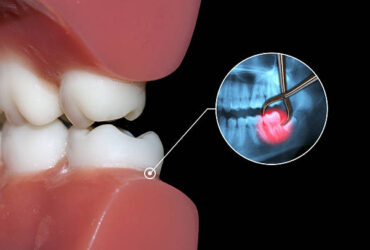

ฟันคุดคือ ฟันกรามซี่ในสุด ทั้งหมด 4 ซี่ บน ล่าง ซ้าย ขวา ไม่สามารถขึ้นได้ตามปกติเพราะพื้นที่ไม่เพียงพอให้ฟันสามารถขึ้นมาได้ บางซี่อาจจะโผล่ขึ้นมาเล็กน้อย และบางซี่ถูกฝั่งอยู่ในกระดูดขากรรไกร อาจจะขึ้นตรง เอียงหรือนอนในแนวราบส่วนใหญ่ฟันคุดมักพบว่าอยู่ที่ฟันกรามซี่ล่างในสุดและพบมากสุดในช่วงอายุ ประมาณ 16 – 25 ปี หรืออาจจะช้ากว่านั้น